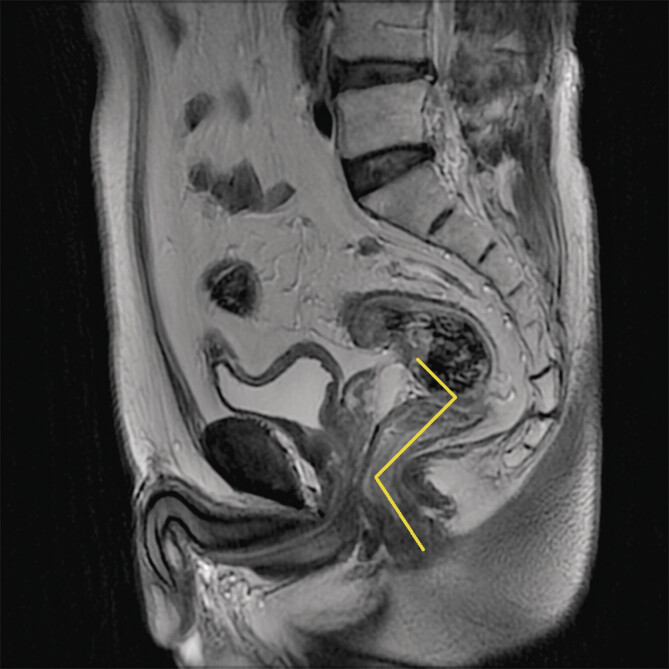

Purpose: This study aimed to measure the precise distance from the lowest boundary of a rectal tumor to the anal verge (DTAV) in patients with rectal cancer.

Materials and methods: A retrospective analysis was performed on clinical data from 70 rectal cancer patients. DTAV measurements were collected using transrectal biplane ultrasound, MRI, and colonoscopy.

Conclusion: Transrectal biplane ultrasound utilizing EFOV imaging technology exhibited both accuracy and reproducibility for measuring DTAV. This approach provided a highly efficient and practical clinical tool for DTAV measurement.

Abstract Image